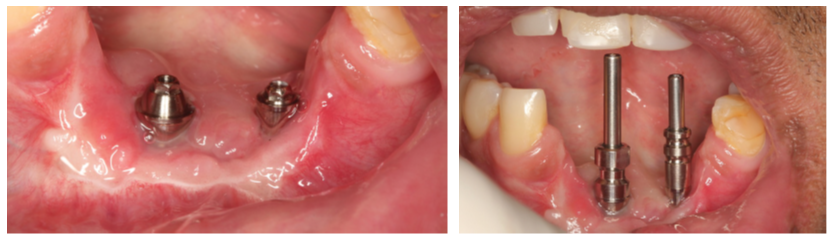

A cirurgia de reconstrução óssea estava contraindicada devido à qualidade ruim dos tecidos moles. Por conta disso, foi planejada uma cirurgia guiada para evitar o descolamento do tecido mole que fatalmente teria muita dificuldade para ter uma reparação satisfatória.

A escolha foi pelo implante Cone Morse Maestro, pois o osso era muito cortical e a macrogeometria do implante Maestro permite a colocação com um torque menor.

A cirurgia guiada foi fundamental na resolução desse caso, pois uma cirurgia com incisão e descolamento de tecido mole traria muitas dificuldades para a cicatrização.